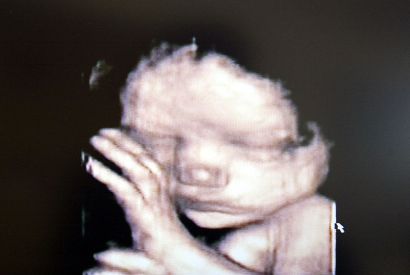

Politicians need to listen on abortion laws

Occasionally a politician proposes something so mind-bogglingly extreme and dangerous that it’s hard to fully believe they’re actually being serious.…